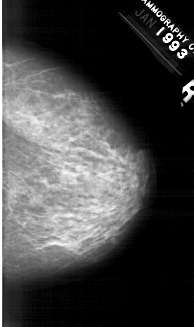

A_1259_1.LEFT_CC

LEFT_CC LINES 6106 PIXELS_PER_LINE 3166 BITS_PER_PIXEL 12 RESOLUTION 43.5 OVERLAY